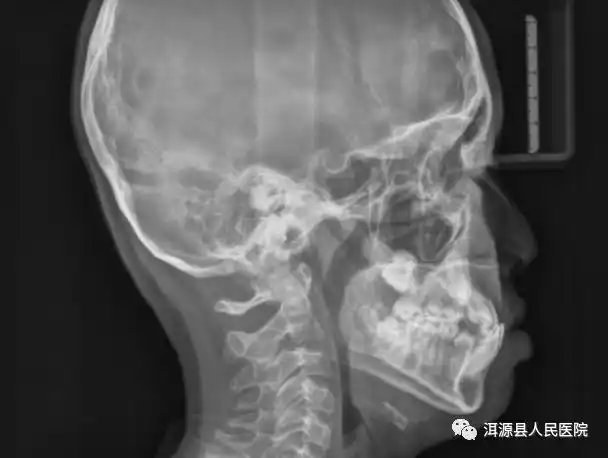

头颅侧位片可用于口腔正畸,正颌治疗前,中,后牙及颌骨相对位置的改变

头颅侧位片侧方位展现牙骨位置,通常拍摄曲面断层片的机器也可以拍摄